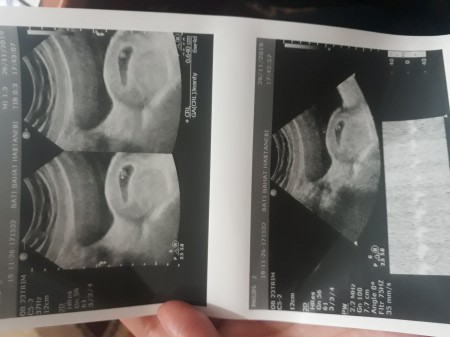

Ultrason Goruntusu Nasil Okunur 9 Adim Resimlerle Wikihow